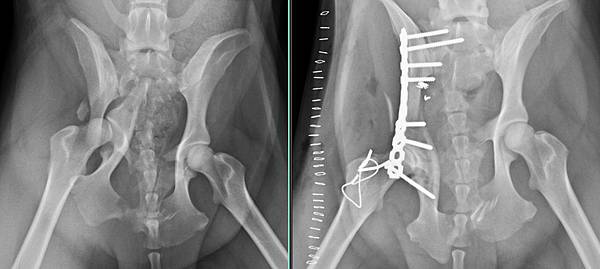

車禍後無法移動

檢查發現骨盆粉碎性骨折

手術修復後